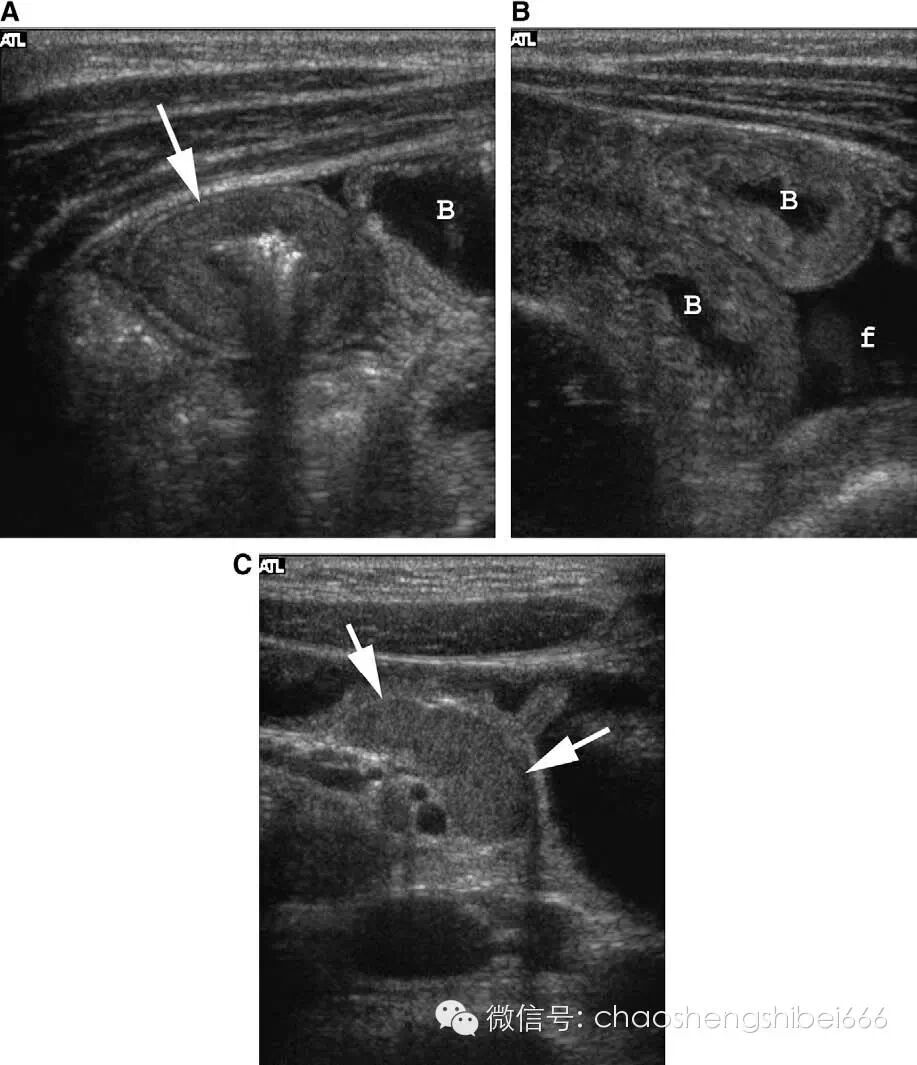

正常的阑尾直径小于等于6mm且有可压缩性(图2),不正常的阑尾通常直径大于等于7mm并且不可压缩(图3)。阑尾是一个管状的盲端,阑尾内的粪石可以也可不显示(图4)。如果阑尾确实存在异常,检查具有可重复性,即移走探头再重复扫查仍然可以找到病变。彩色多普勒超声显示血流增多也可提示存在炎症。在穿孔的病例,可能无法显示阑尾结构,而只见到包块或者脓肿。虽然这些结果不具有特异性,但是由于此种情况下最可能的诊断仍是阑尾炎,所以要考虑阑尾穿孔的可能。

2 11岁女孩的正常阑尾(箭头所示)。阑尾直径4mm,小箭头为阑尾尖端。A长轴图像,B短轴图像。

3 5岁男孩的非穿孔性阑尾炎声像图。长轴(A)和短轴(B)图像均可见肿胀阑尾(箭头),直径12mm。小箭头示阑尾尖端。

4 5岁女孩的阑尾炎穿孔声像图。可见阑尾粪石(箭头)伴声影(小箭头)。粪石周围的软组织为阑尾壁,但阑尾结构未显示。